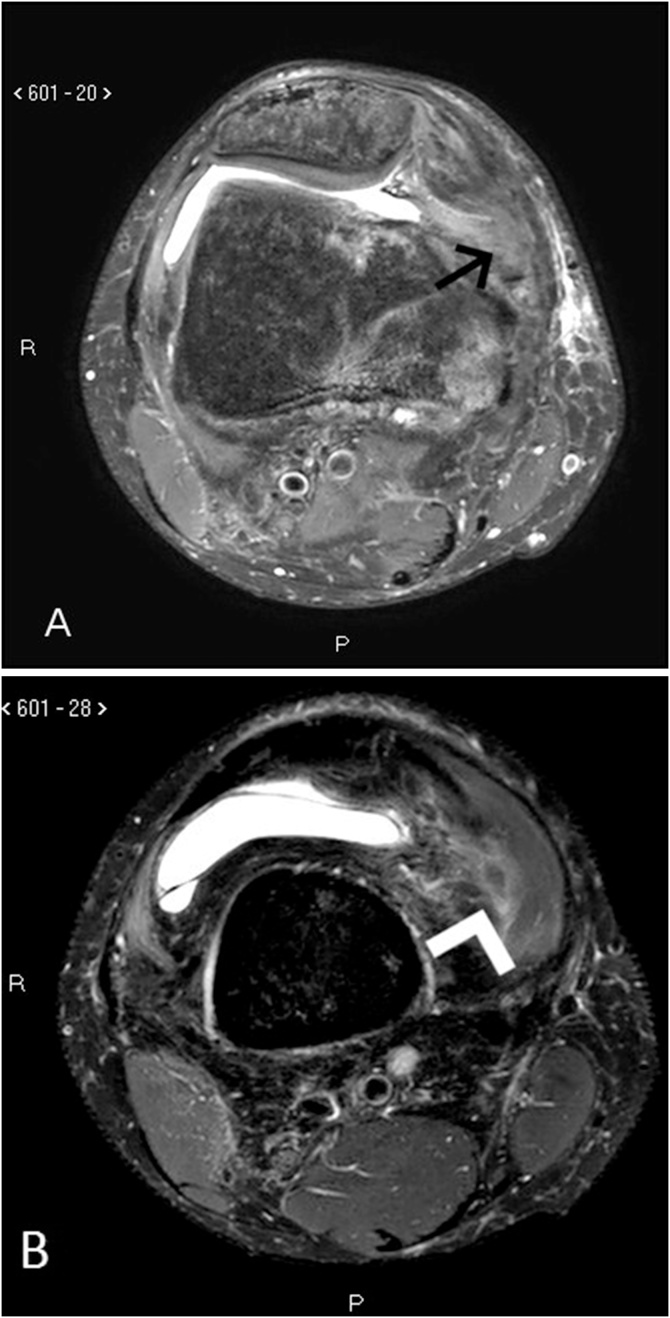

Fig. 3.

Axial knee magnetic resonance imaging (MRI) in T2 SPAIR sequence: abnormalities of MPFL (A) at the femoral attachment (arrow), and signs of vastus medialis oblique (VMO) fibers strain (B) (arrowhead).